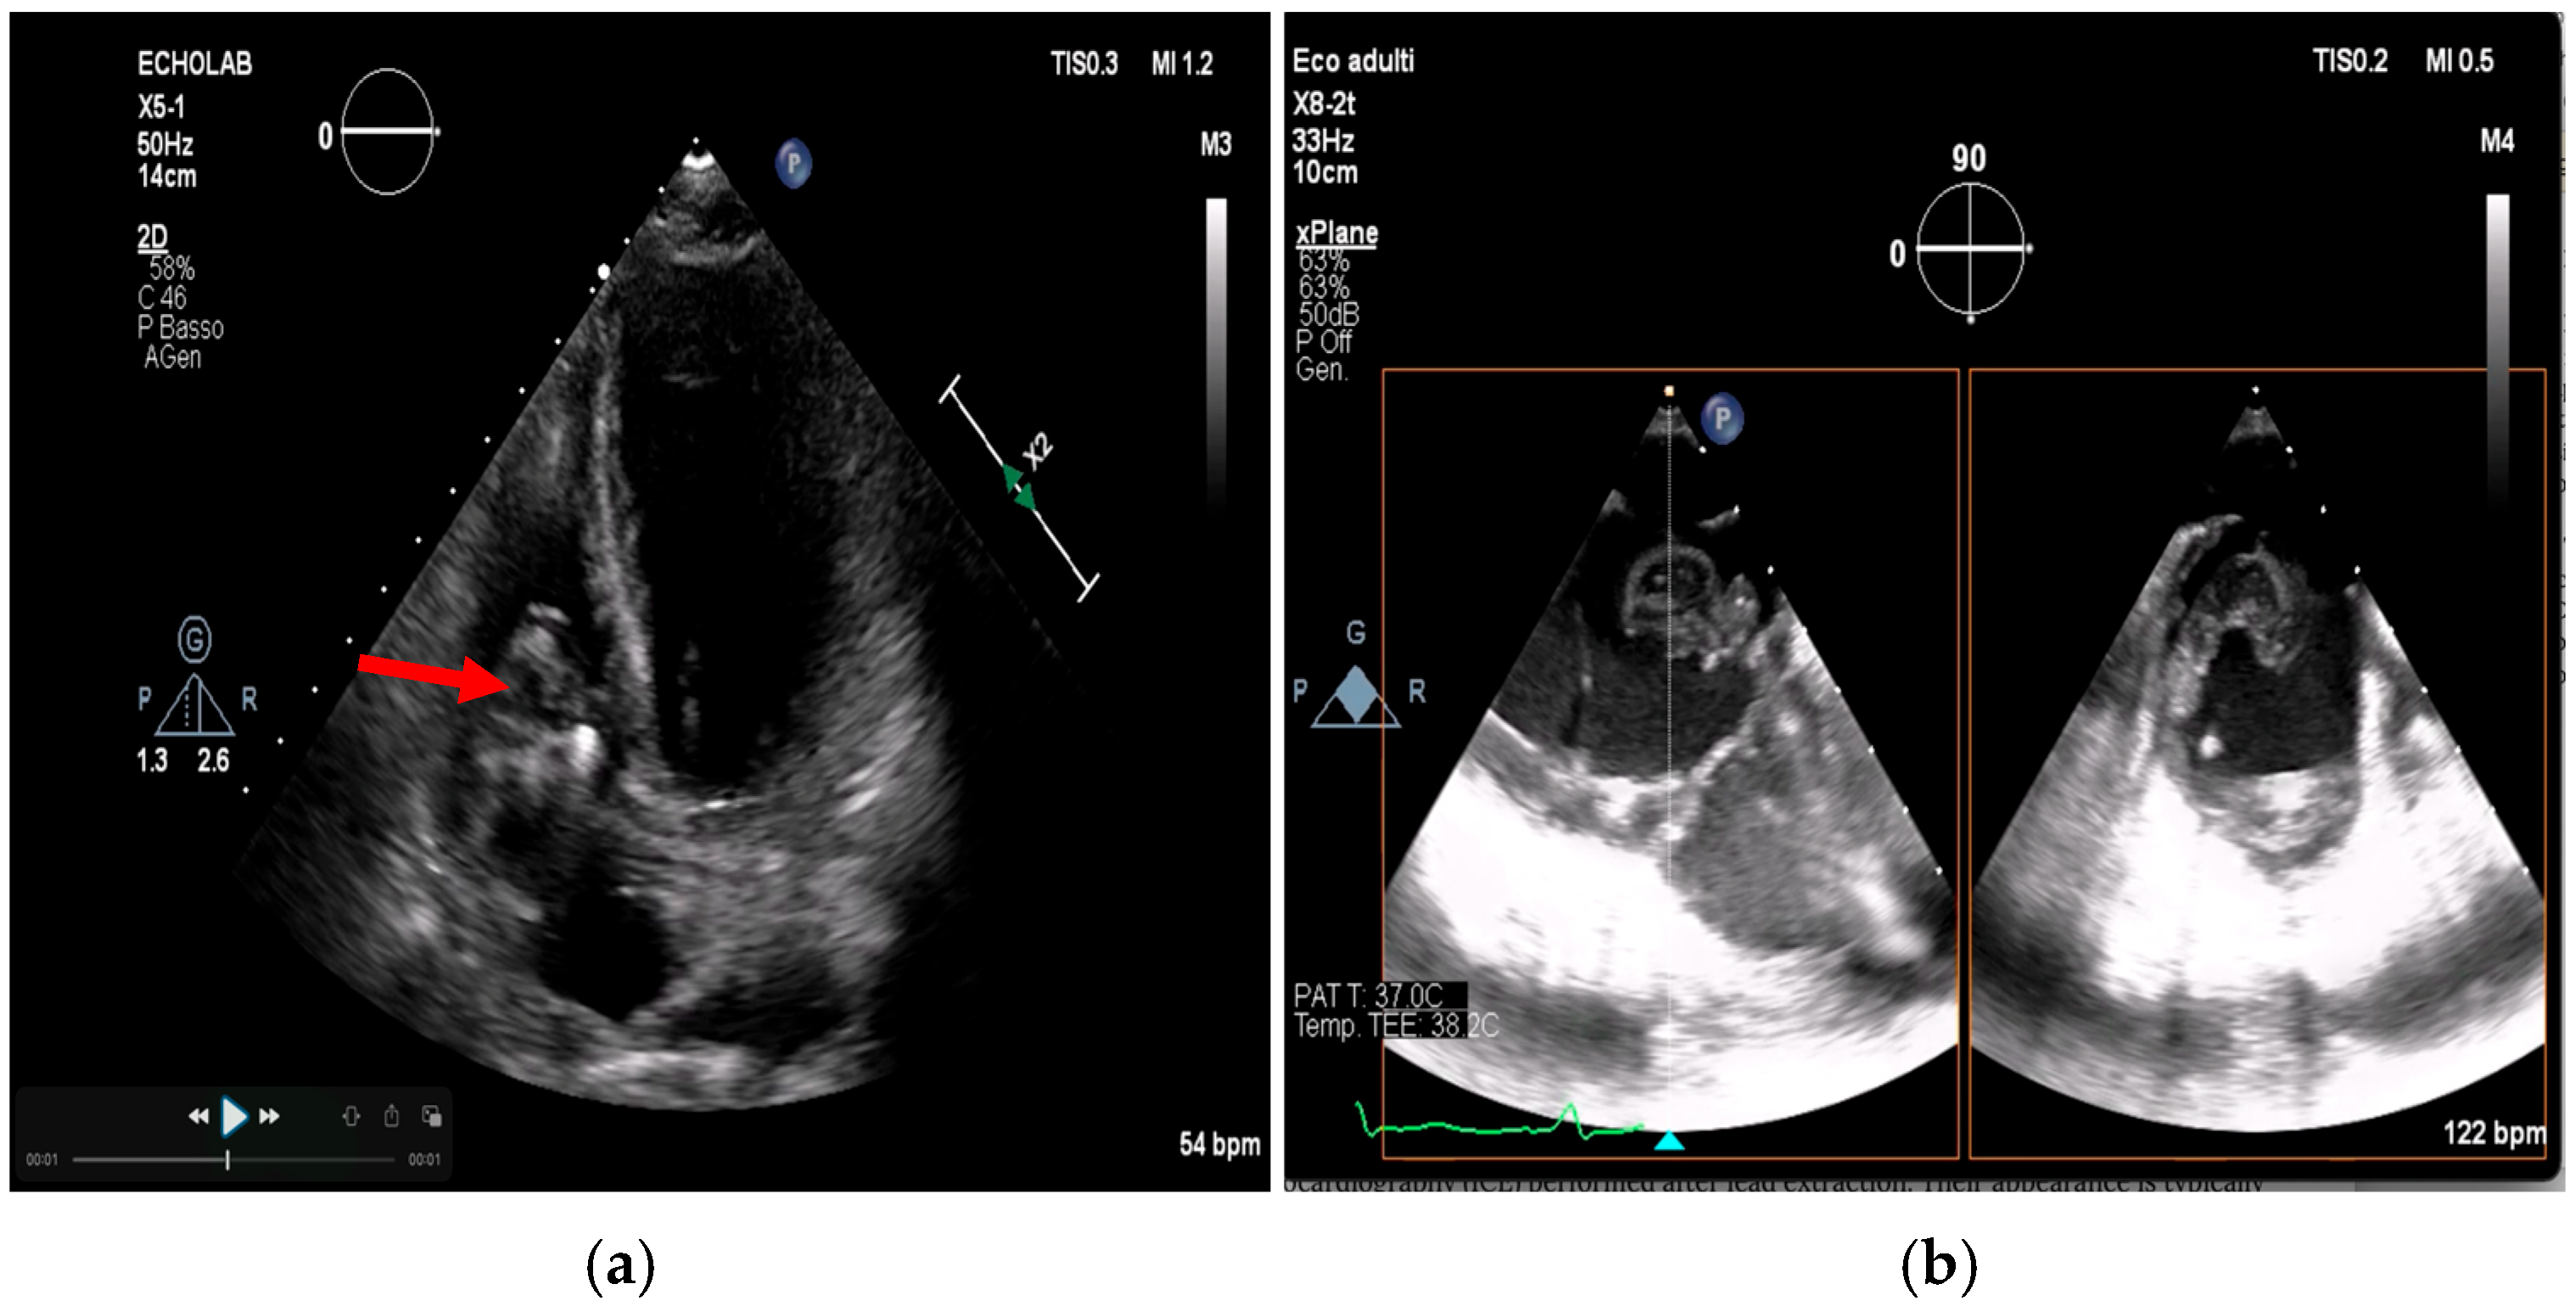

- Poterała, M.; Kutarski, A.; Brzozowski, W.; Tomaszewski, M.; Gromadziński, L.; Tomaszewski, A. Echocardiographic assessment of residuals after transvenous intracardiac lead extraction. Int. J. Cardiovasc. Imaging 2020, 36, 423–430. [Google Scholar] [CrossRef]

- Narducci, M.L.; Di Monaco, A.; Pelargonio, G.; Leoncini, E.; Boccia, S.; Mollo, R. Presence of ‘ghosts’ and mortality after transvenous lead extraction. Europace 2016, 19, 432–440. [Google Scholar] [CrossRef][Green Version]

- Le Dolley, Y.; Thuny, F.; Mancini, J.; Casalta, J.-P.; Riberi, A.; Gouriet, F. Diagnosis of Cardiac Device–Related Infective Endocarditis After Device Removal. JACC Cardiovasc. Imaging 2010, 3, 673–681. [Google Scholar] [CrossRef]

- Li, Y.; Jiang, L.; Wang, L.; Han, Q.; Yin, X.; Feng, Y. Ghost in the right atrium: A case report on successful identification of residual fibrous tissue. Heliyon 2023, 9, e21982. [Google Scholar] [CrossRef] [PubMed]